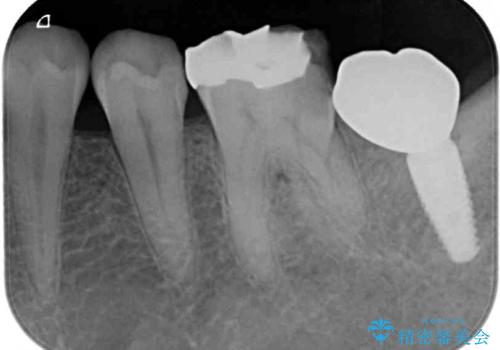

- 左下の歯が欠けてしまったとのことで来院された患者様です。

大きな銀歯が装着されており、その周りからむし歯が広がっている状態でした。

特に症状はなく、神経組織も健全な状態であったため、むし歯を全て取り切った後にフルジルコニアクラウンにて補綴することとしました。